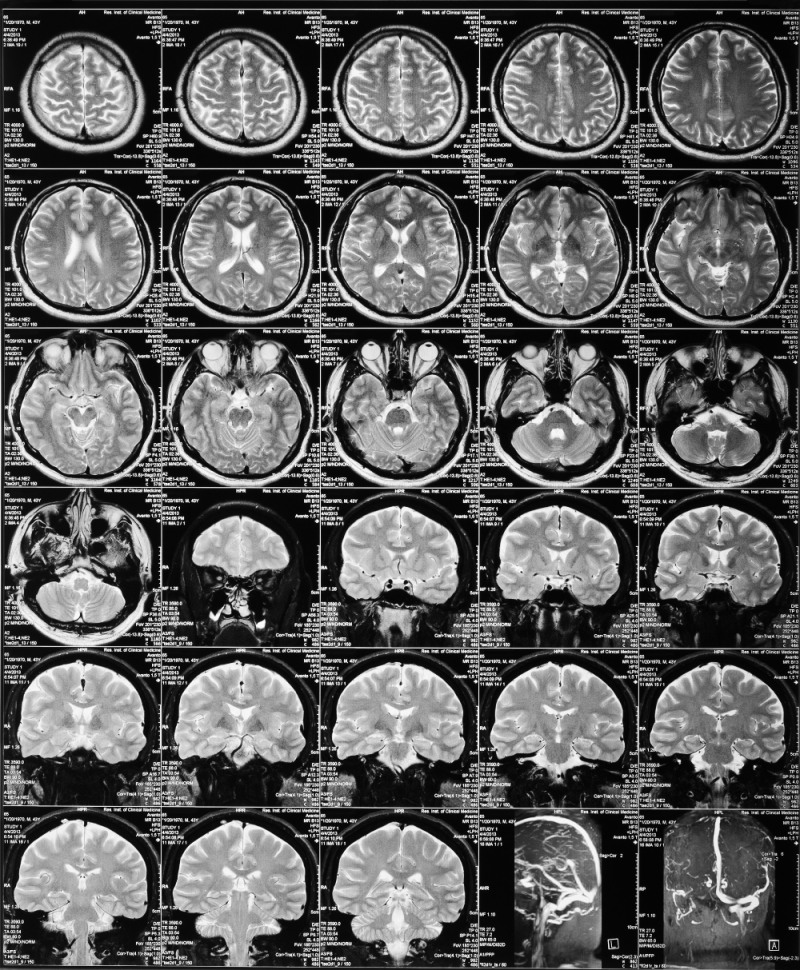

아밀로이드 PET 검사는 뇌 안의 베타아밀로이드를 영상화할 수 있는 치매뇌영상검사로 경도인지장애 환자가 향후에 치매로 전환될 위험을 예측하는데 유용하게 이용되는 검사이고, 결과가 양성이면 향후 치매발병확률이 높아진다. 고비용 (100~150만원)의 뇌영상 검사이기에 치매가 발병되지 않은 환자에게 권하기 어렵다.